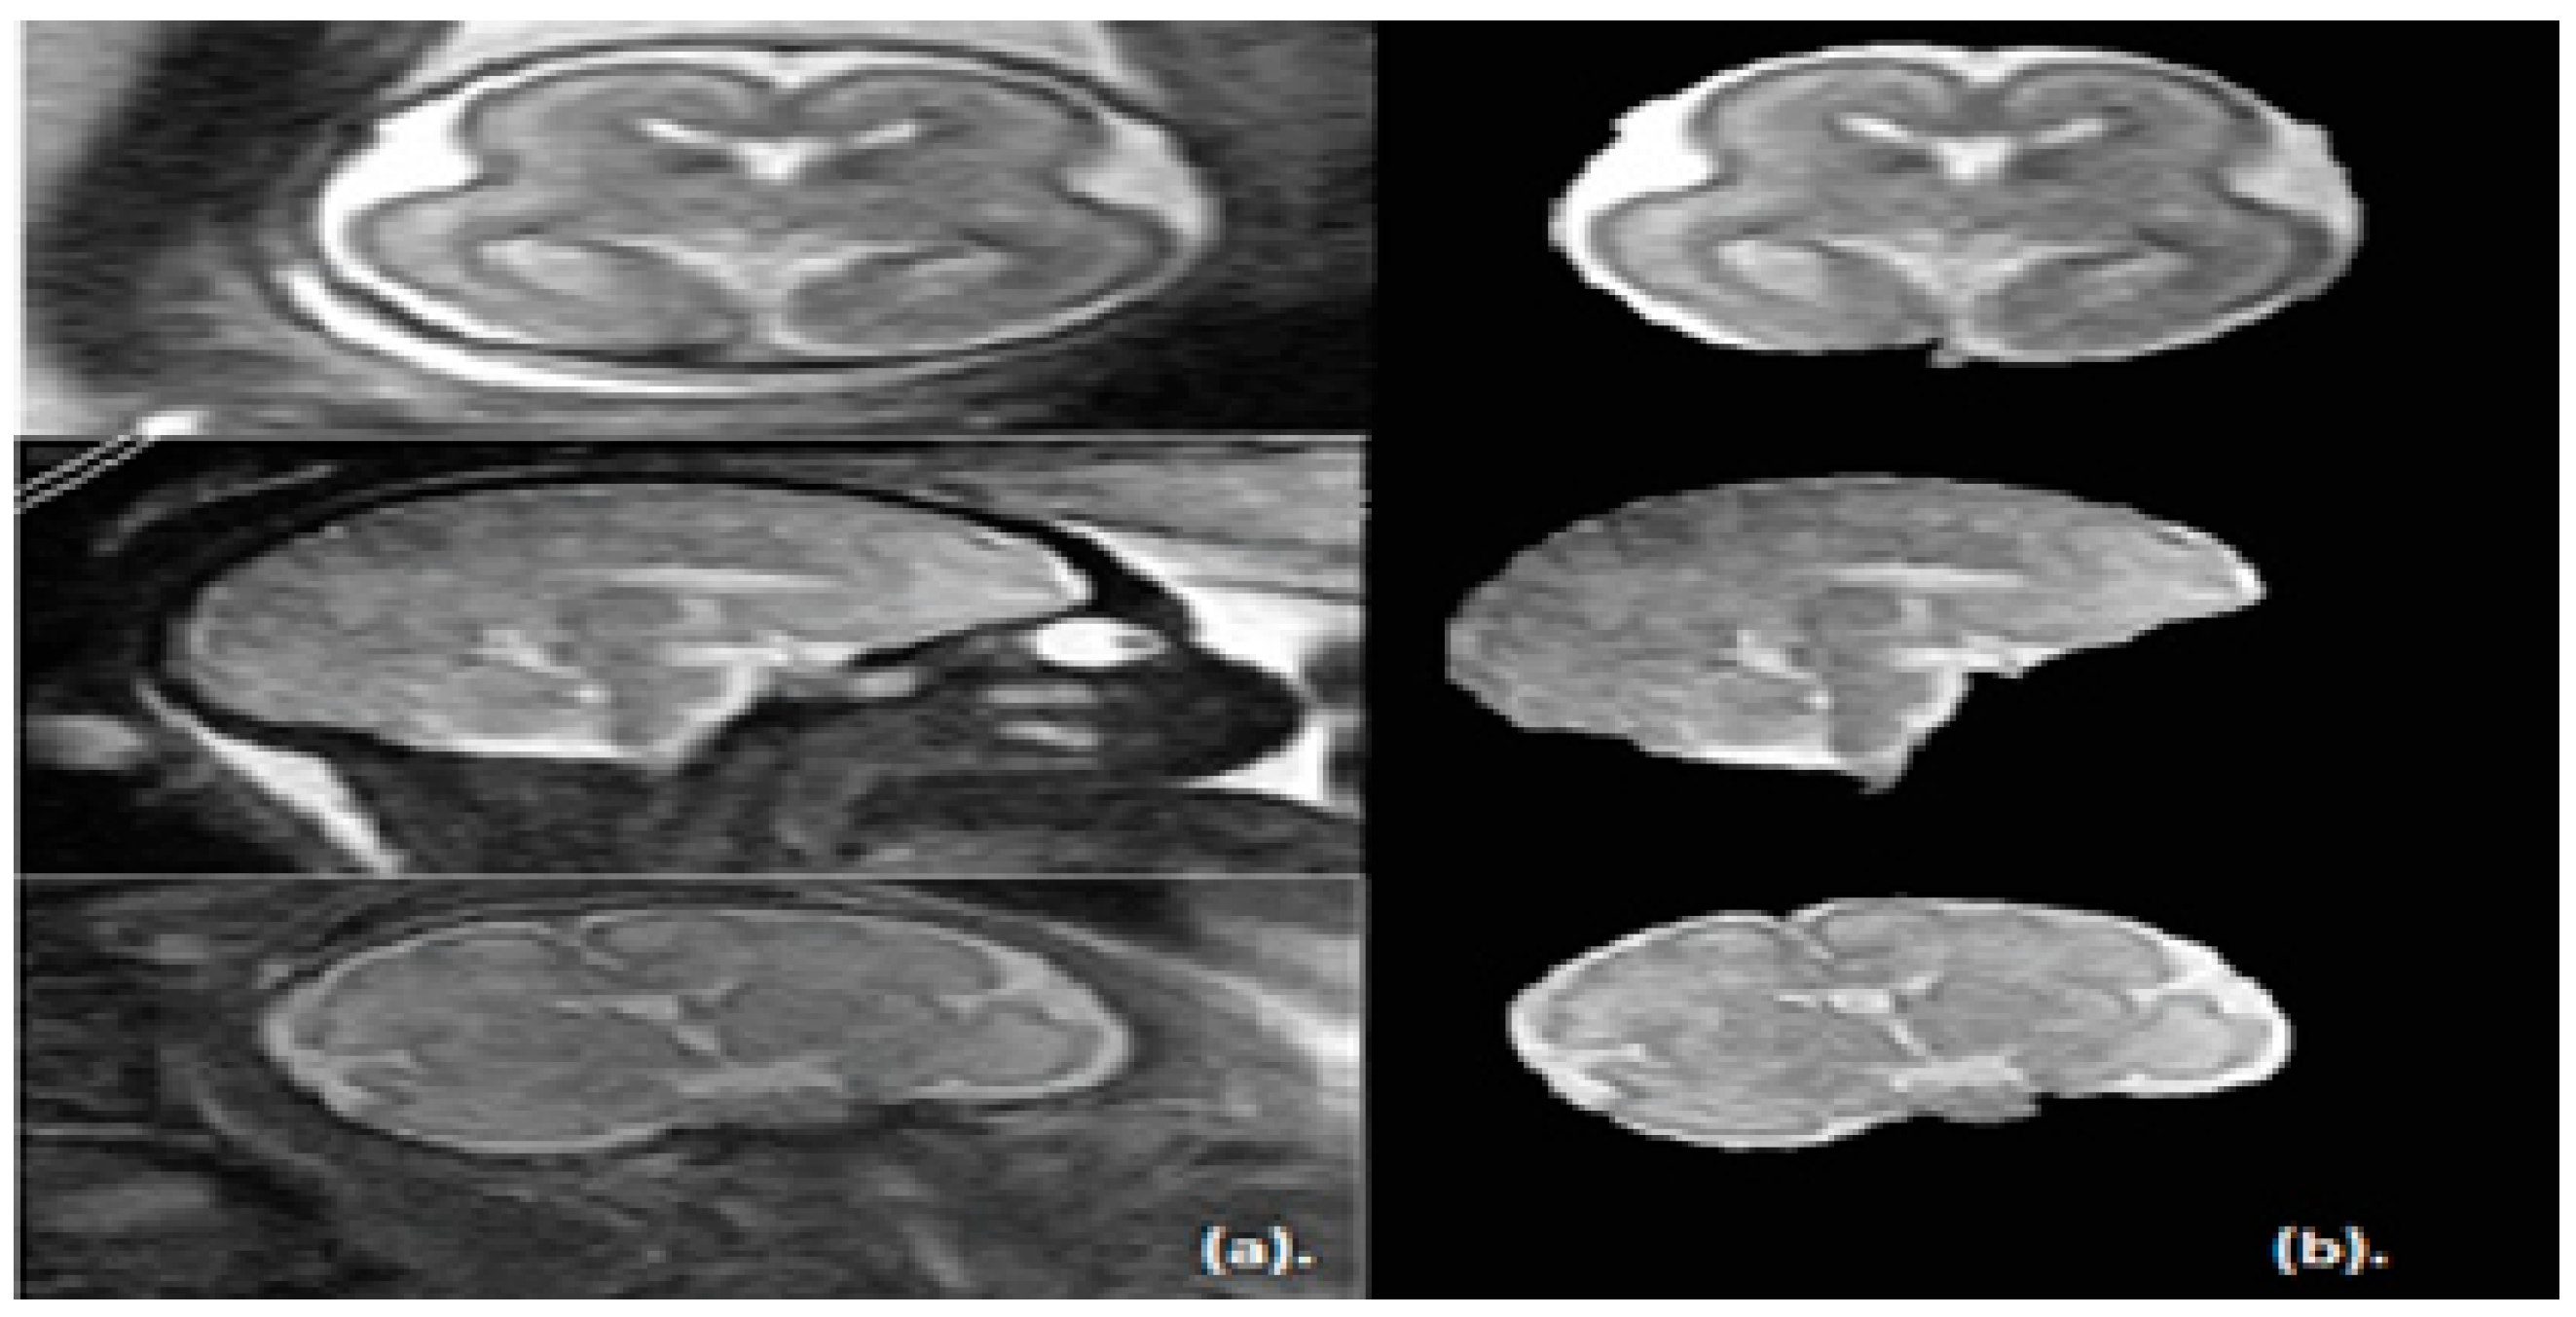

Coronal Sagittal And Axial Slices Of The Brain Depicting The Regions Download Scientific Diagram

Corte Coronal Axial E Sagittal De Imagens De Rm Destacando As Download Scientific Diagram